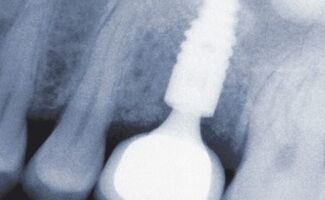

Zahnimplantate sind künstliche Zahnwurzeln, die fest im Kiefer verankert werden. Darauf wird anschließend der sichtbare Zahnersatz befestigt. Das Ergebnis: Ein sicherer Halt und ein natürliches Gefühl beim Kauen und Sprechen.

2. Einsetzen des Implantats

Schonender Eingriff unter örtlicher Betäubung

3. Einheilphase

Das Implantat verbindet sich fest mit dem Kieferknochen